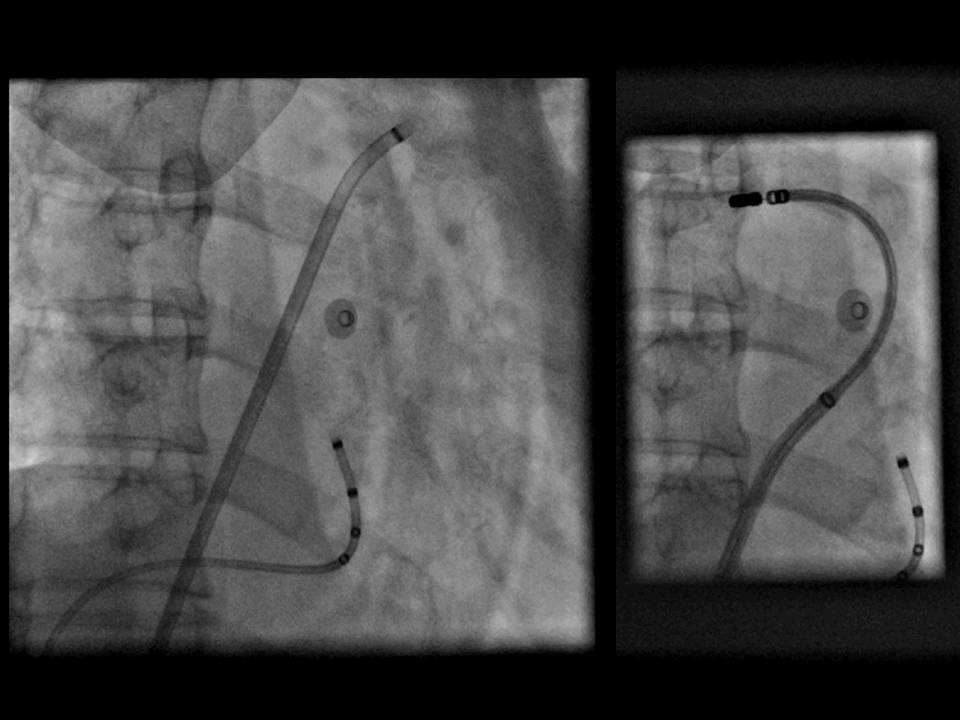

肺静脉隔离术难点